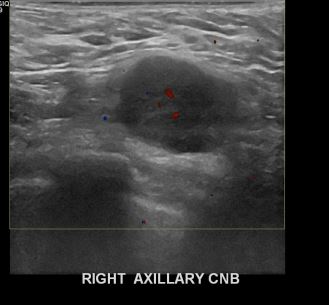

아산유외과 개원후 654번째 유방암진단

상기환자 외부검사상 이상소견으로 내원하신 40대여성으로 유방암으로 림프절 전이의심되어 조직검사시행해 유방암 진단되었습니다.